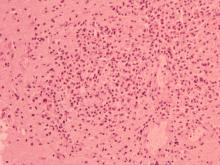

肺:肺水腫,局部肉芽腫病灶,壞死區內有大量炎症細胞浸潤,以單核球和巨大細胞為主。在許多Giant cell中可見褐色不易染色的黴菌菌體。局部壞死區近血管處可見膽固醇裂隙浸潤。 2.

肝:大區域瀰漫性壞死,肝索排列凌亂,多數巨大細胞浸潤,並可見多數黴菌樣菌體出現。 3.

脾與淋巴結:多發局部肉芽腫,淋巴球減少流失,大量吞噬球及巨大細胞浸潤於壞死灶,內含多數黴菌樣菌體。 4.